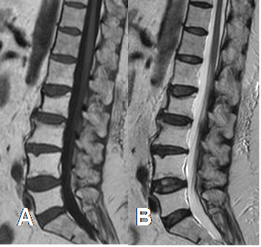

Fig 206. Cambios por radioterapia.

A: RM sagital en T1 y B: RM sagital en T2. Gran hiperintensidad en ambas secuencias de las vértebras L1 a L5, por conversión a MO grasa, secundaria a radioterapia.